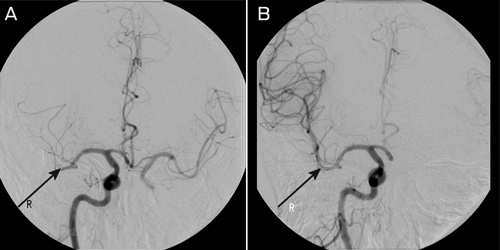

A clot retrieval device (Solitaire AB Neurovascular Remodeling Device, 4 × 15 mm; ev3 Inc, Irvine, Calif, USA) was used to achieve reperfusion to the right MCA beyond the M2 segment (Box 3). The procedure was performed under general anaesthesia. Initial diagnostic imaging was performed using a 5-French diagnostic catheter and heparin (3000 IU) was delivered intravenously. A 6-French shuttle sheath (Cook Medical, Brisbane, Qld) was positioned within the common carotid artery, and then a 6-French neuron guide catheter was positioned within the inferior right internal carotid artery. A Transcend floppy guidewire (0.014"; Boston Scientific, Natick, Mass, USA) and Rebar 18 microcatheter (ev3 Inc, Irvine, Calif, USA) were advanced into the right MCA and two occluded branches selected. The microguidewire was passed through the thrombus and the microcatheter was advanced over the wire about 5 mm beyond the thrombus. The position of the microcatheter was confirmed by contrast injection. The stent was then advanced to the distal tip of the microcatheter and then unsheathed, both within and just beyond the thrombus. The distal microcatheter marker was positioned proximal to the uncovered stent. The unsheathed Solitaire AB stent and microcatheter were removed as a unit while suction was applied to the guiding catheter. This procedure was repeated with each pass. Angiographic assessment was performed after each pass with the Solitaire AB stent to assess for revascularisation status, vessel trauma or distal emboli. Two passes as described using the Solitaire AB stent were performed within each of the two affected vessels achieving TIMI (Thrombolysis In Myocardial Infarction) grade 2 flow or better.